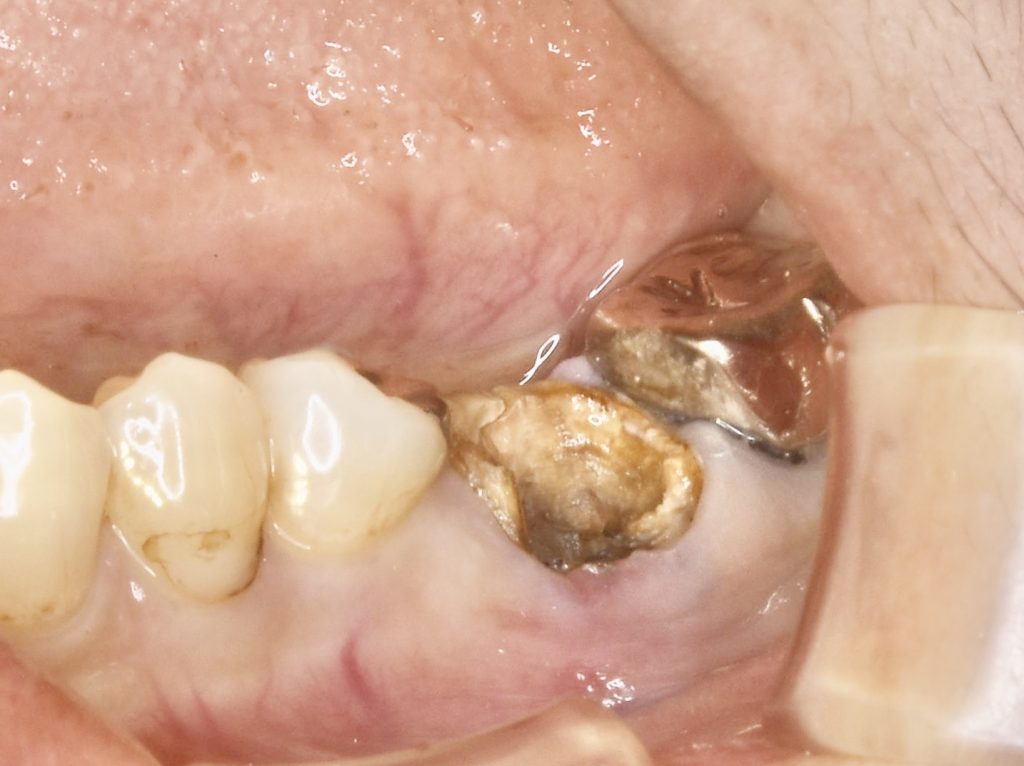

歯根破折を起こし、周囲の骨が炎症を起こしていました。

骨の再生のみならず、歯肉も不足していた為、歯肉移植を行いメンテナンスしやすい環境を整えました。